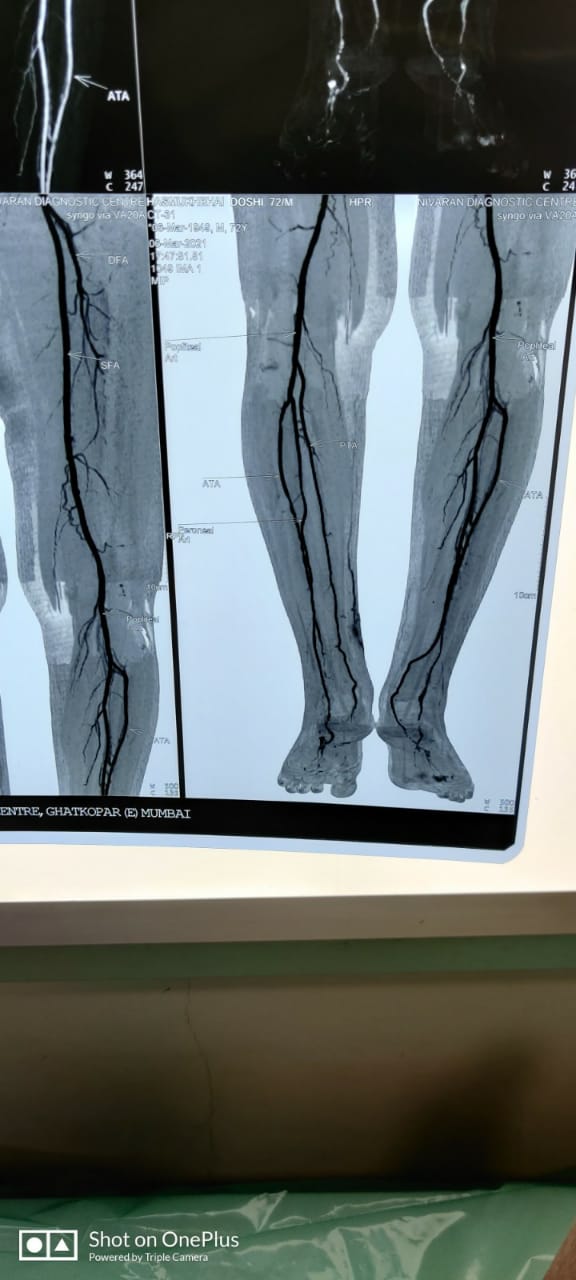

Patient’s Successfully Treated with Diabetic Foot Problems